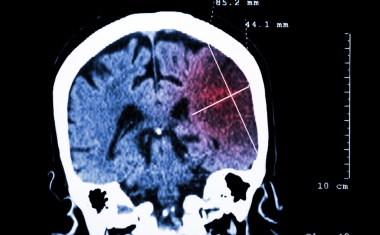

Telemedizin: Beurteilung von CT-Bildern aus der Ferne in hoher Qualität möglich

13.02.2013 - Speziell für die telemedizinische Versorgung von Schlaganfallpatienten geschulte Neurologen können auch von einem anderen Ort aus in guter Qualität CT-Bilder von akut betroffenen...